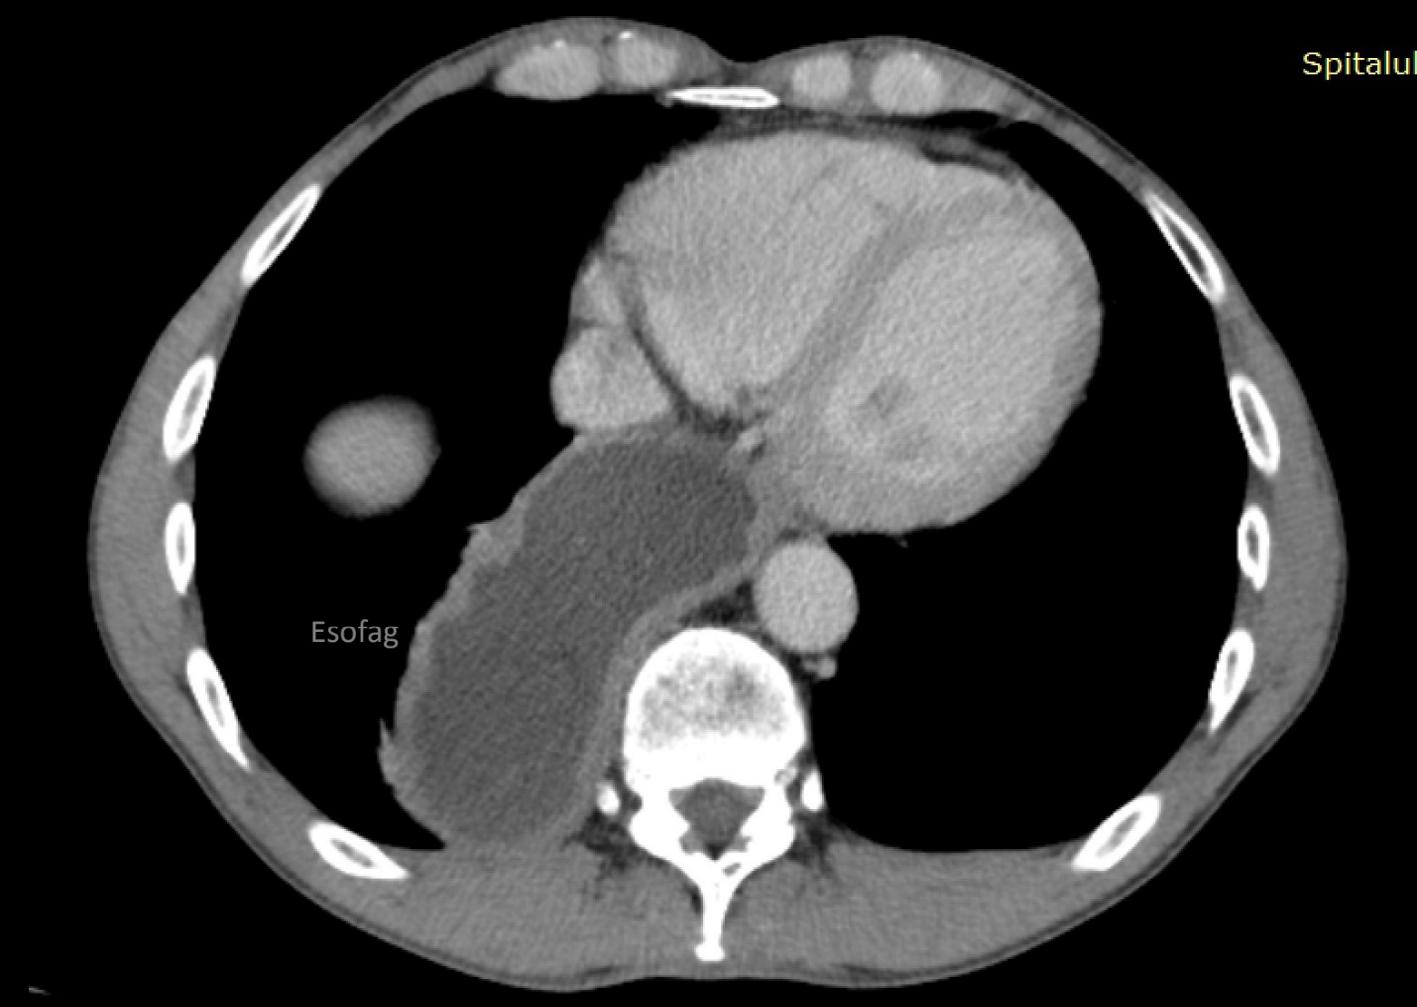

Biopsia limfoganglionului santinelă în cancerul mamar Dr. Ileana Popa, Dr. Emil Popa

Emil Popa

Medic primar chirurgie generală, doctor în ştiinte medicale, FACS, Clinica de chirurgie generală Spitalul Clinic Colțea, Bucureşti

Medic primar anatomie patologică, doctor în ştiinte medicale, Serviciul de anatomie patologică Spitalul Clinic Colțea, Bucureşti

Dr. Ileana Popa